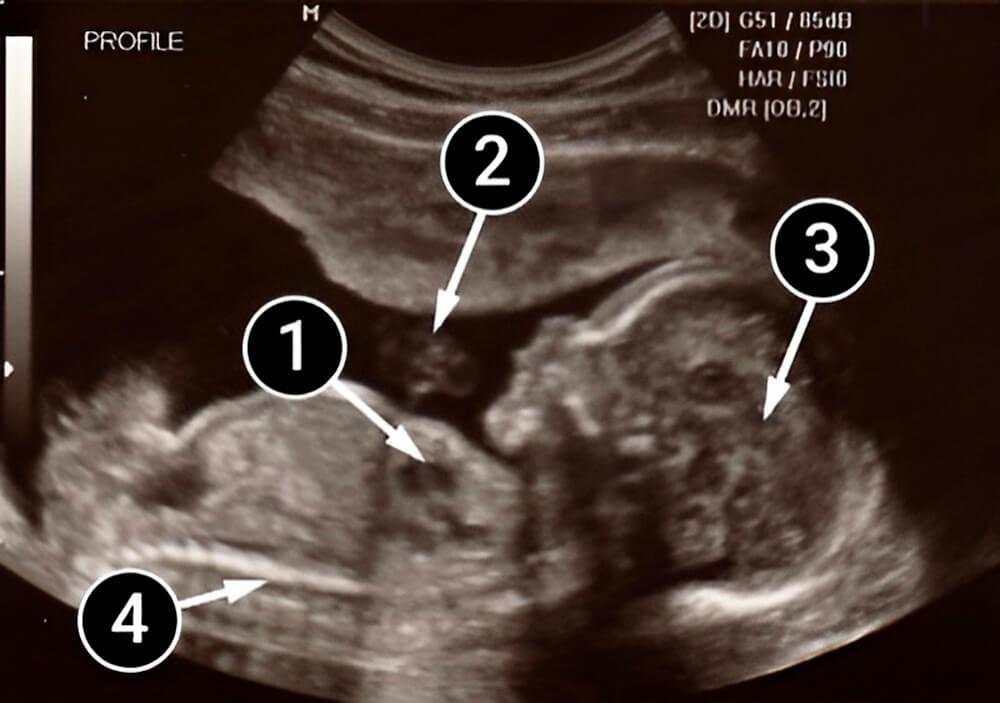

El bebé está acostado boca arriba, apoyado contra el útero, lo que hace que la columna sea visible a través del ultrasonido. El cordón umbilical, con una vena y dos arterias, aparece en la oscuridad del líquido amniótico. Una mancha oscura en el pecho revela el corazón y los vasos sanguíneos. Aparece un diafragma en forma de tira y el hígado y los intestinos son visibles en la cavidad abdominal.

Contra la placenta podemos ver la cabecita redonda y estructurada del bebé. Los huesos del cráneo protegen al creciente cerebro. Los hemisferios grandes del cerebro ya son visibles, al igual que el plexo de fibras nerviosas que los conectan (el cuerpo calloso).

La estructura facial, la nariz y los labios son claramente visibles en la imagen. También podemos ver su pequeño cuello, pues la barbilla del bebé ya no está presionada contra su pecho.

corazón

cordón umbilical

cerebro

columna vertebral